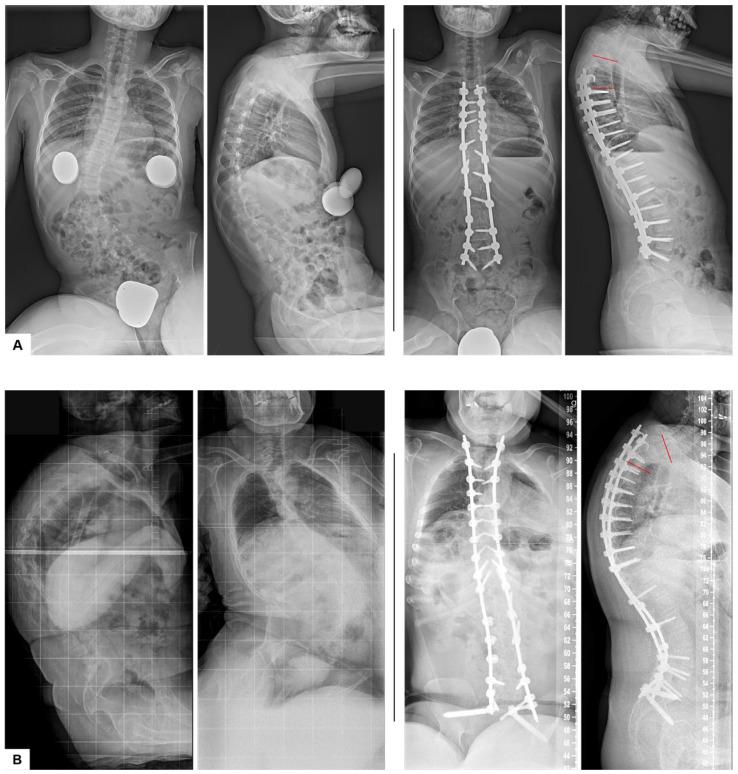

Proximal junctional kyphosis (PJK) is one of the most frequently discussed complications following corrective surgery in patients with neuromuscular scoliosis (NMS). Despite its clinical relevance, the etiology of PJK remains incompletely understood and appears to be multifactorial. Biomechanical and limited clinical studies suggest that preoperative hyperkyphosis, resection of the spinous processes with consequent disruption of posterior ligamentous structures, and rod contouring parameters may contribute as risk factors. : To validate these findings, we retrospectively analyzed 99 NMS patients who underwent posterior spinal fusion using a standardized screw-rod system between 2009 and 2017. Radiographic assessments were conducted at three time points: preoperatively (preOP), postoperatively (postOP), and at a mean follow-up (FU) of 29 months. Clinical variables collected included patient age, weight, height, sex, and Risser sign. Radiographic evaluations encompassed Cobb angles, thoracic kyphosis (TK), lumbar lordosis, the levels of the upper (UIV) and lower (LIV) instrumented vertebrae, the total number of fused segments, parameters of sagittal alignment, the rod contour angle (RCA), and the postoperative mismatch between RCA and the proximal junctional angle (PJA). Based on the development of proximal junctional kyphosis, patients were categorized into PJK and non-PJK groups. : The overall incidence of PJK was 23.2%. In line with previous biomechanical findings, spinous process resection was significantly associated with PJK development. Furthermore, the PJK group demonstrated significantly higher preoperative TK (59.3° ± 29.04° vs. 34.5° ± 26.76°, < 0.001), greater RCA (10.2° ± 4.01° vs. 7.7° ± 4.34°, = 0.021), and a larger postoperative mismatch between PJA and RCA (PJA-RCA: 3.8° ± 6.76° vs. -1.8° ± 6.55°, < 0.001) compared to the non-PJK group. : Spinous process resection, a pronounced mismatch between postoperative PJA and RCA (odds ratio [OR] = 1.19, = 0.002), excessive rod bending (i.e., high RCA), and severe preoperative thoracic hyperkyphosis with an expected increase in the risk of PJK of approximately 6.5% per degree of increase in preoperative TK are significant risk factors for PJK. These variables should be carefully considered during the surgical planning and execution of deformity correction in NMS patients.

近端交界性后凸畸形(PJK)是神经肌肉型脊柱侧凸(NMS)患者矫正手术后最常被讨论的并发症之一。尽管其具有临床相关性,但PJK的病因仍未完全明确,似乎是多因素的。生物力学和有限的临床研究表明,术前脊柱后凸增加、棘突切除导致后韧带结构破坏以及棒材塑形参数可能是危险因素。为了验证这些发现,我们回顾性分析了99例在2009年至2017年间使用标准化螺钉 - 棒系统进行后路脊柱融合的NMS患者。在三个时间点进行影像学评估:术前(preOP)、术后(postOP)以及平均随访(FU)29个月时。收集的临床变量包括患者年龄、体重、身高、性别和Risser征。影像学评估包括Cobb角、胸椎后凸(TK)、腰椎前凸、上固定椎(UIV)和下固定椎(LIV)的节段、融合节段总数、矢状面排列参数、棒材塑形角度(RCA)以及术后RCA与近端交界角(PJA)之间的不匹配。根据近端交界性后凸畸形的发生情况,将患者分为PJK组和非PJK组。PJK的总体发生率为23.2%。与先前的生物力学研究结果一致,棘突切除与PJK的发生显著相关。此外,与非PJK组相比,PJK组术前TK显著更高(59.3°±29.04°对34.5°±26.76°,<0.001),RCA更大(10.2°±4.01°对7.7°±4.34°,=0.021),且术后PJA与RCA之间的不匹配更大(PJA - RCA:3.8°±6.76°对 - 1.8°±6.55°,<0.001)。棘突切除、术后PJA与RCA之间明显不匹配(优势比[OR]=1.19,=0.002)、棒材过度弯曲(即高RCA)以及术前严重胸椎后凸增加,术前TK每增加一度PJK风险预计增加约6.5%,是PJK的显著危险因素。在NMS患者的手术规划和畸形矫正手术执行过程中,应仔细考虑这些变量。